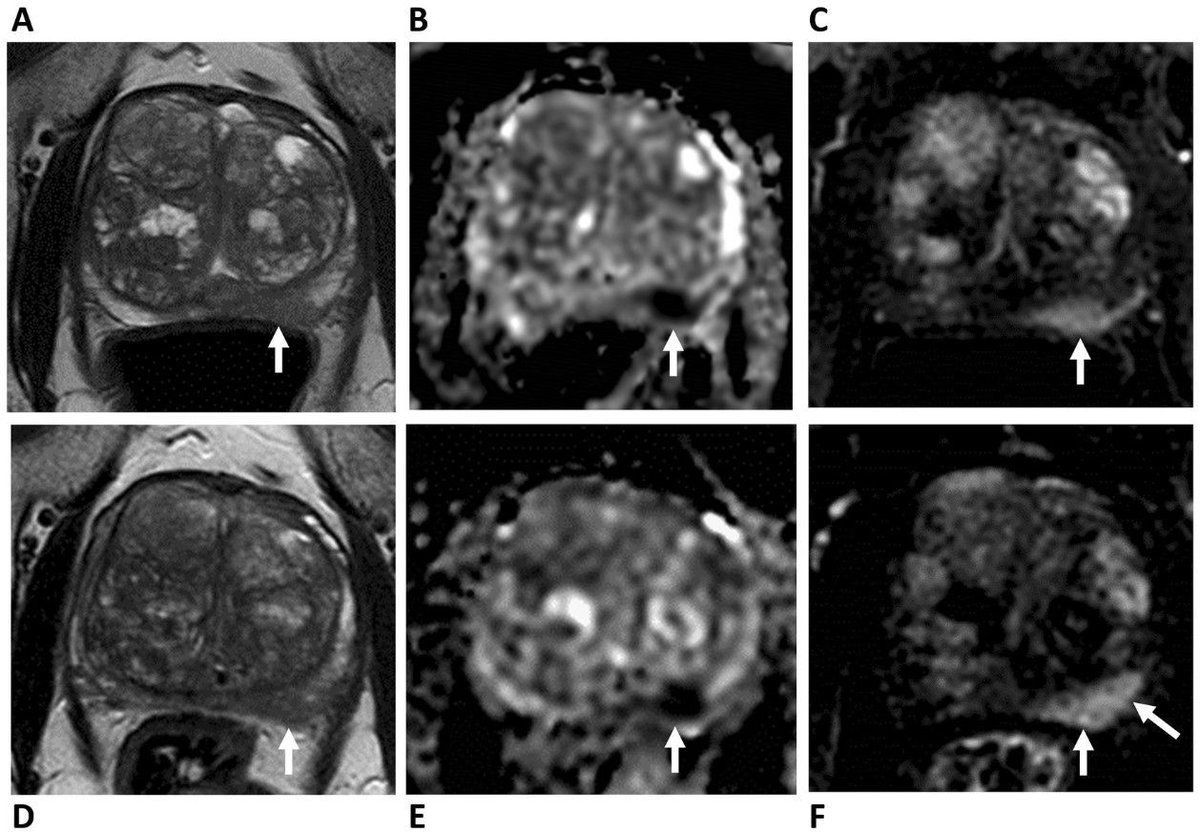

New paper from @FerdiaGallagher. New MRI method reveals details of kidney tumors! 🩻 Our research shows promise for earlier & better diagnosis. Read more: https://t.co/8CJWllJf14 #KidneyHealth #MRI #Radiology

Background Clinical imaging tools to probe aggressiveness of renal masses are lacking, and T2-weighted imaging as an integral part of magnetic resonance imaging protocol only provides qualitative...